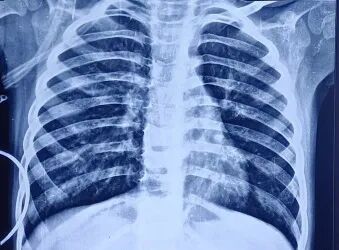

胸片显示双肺野过度充气,伴右肺中野不均匀浸润影及支气管壁增厚(图1)。胸部高分辨率CT扫描显示右肺上叶前段可见厚壁囊腔,可能存在交通,紧邻管壁明显增厚的亚段支气管——提示囊性支气管扩张(图2)。免疫功能缺陷检查已排除:HIV报告正常,免疫球蛋白谱正常,淋巴细胞亚群分析正常。IgA=54.67 mg/dL,IgG=990.32 mg/dL,IgM=404.186 mg/dL,IgE=16.3 IU/mL,CD3(T细胞)=2237.32 个/μL ,62.85% ;CD4 TH细胞=1165.21 个/μL ,32.73% ;CD8 T细胞=1065.26 个/μL,29.92%;CD4/CD8比值1.09均处于正常范围

1  患者入院时胸片显示双肺野过度充气,左肺中野不均匀密度增高影伴支气管周围增厚。